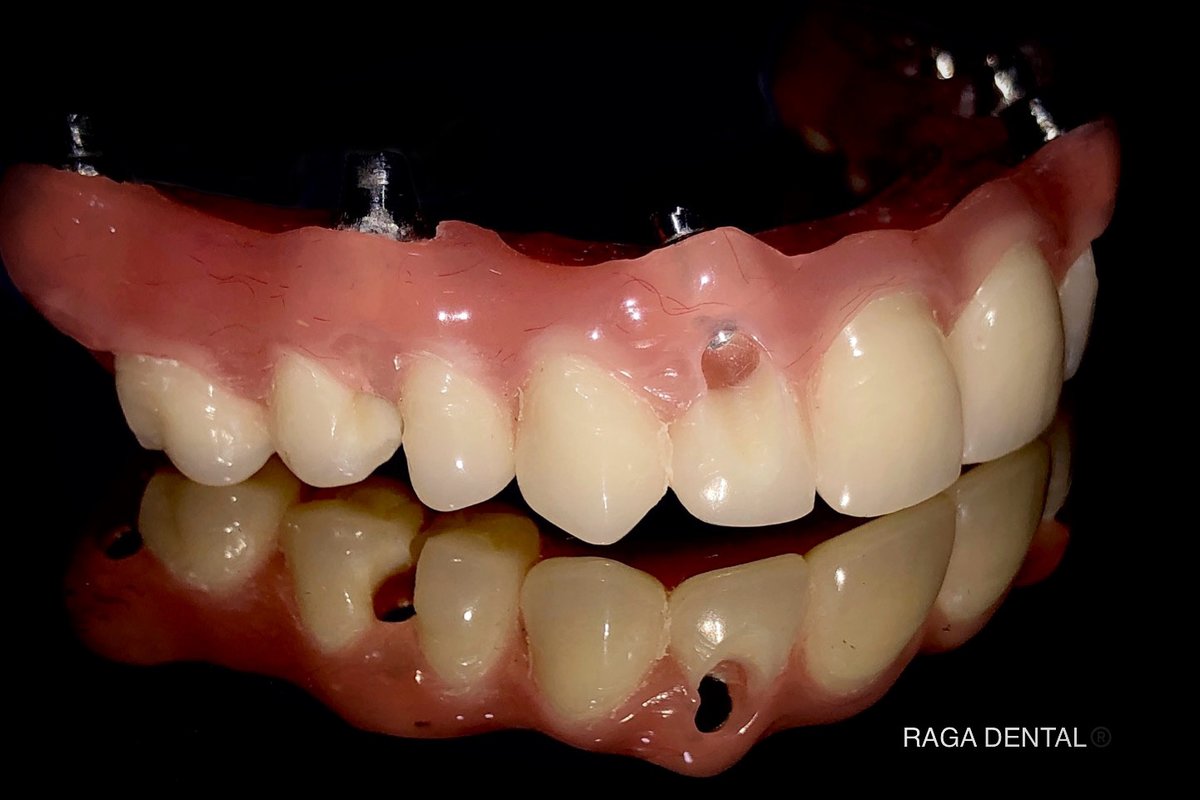

About Raga Dental Center for Dental Implants & Laser Raga Dental is a well established facility with experienced team of doctors , state of the art equipments and especially renowned for Implantology and waterlase Laser Dentistry. We are well equipped with Waterlase Laser, Navident for Navigation implant surgeries, 3D printer for Guided implant surgeries, Phillips zoom whitening for esthetic rehabilitation. We also excel in other ... (Show more)